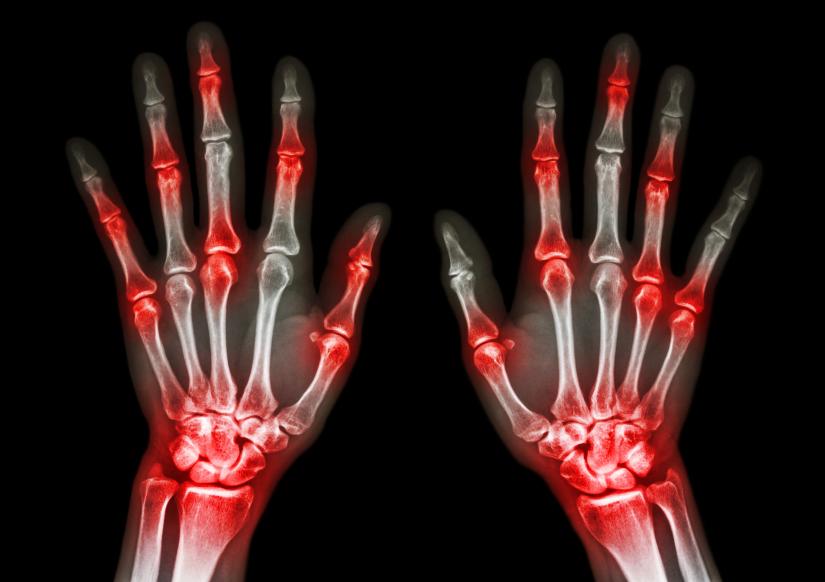

El más visible y principal síntoma de la artritis reumatoide es la inflamación de las articulaciones y el consecuente dolor. Las más afectadas por esta patología son:

• las muñecas

• dedos de manos y pies

La inflamación puede dar lugar a la deformación de las articulaciones, sobre todo cuando la enfermedad está en un estadio avanzado. Y es que el daño en la membrana sinovial hace que los huesos puedan cambiar de posición y se produzca la deformidad.